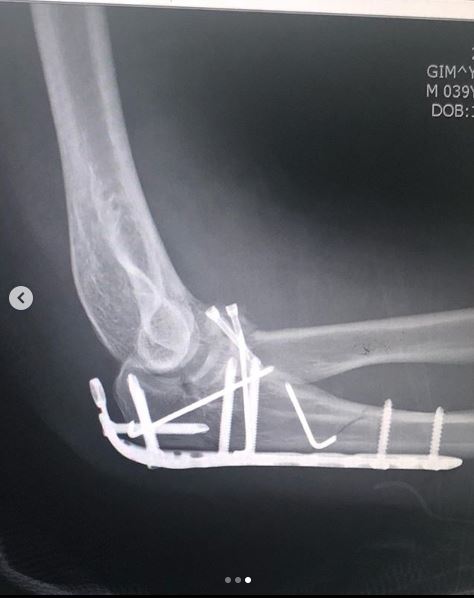

그는 "뜻하지 않게 로봇팔이 되어버렸다"며 "좋은 의료진분들 덕에 수술은 잘 됐다"는 멘션을 첨부했는데요.

사진 속 개코는 병실 침대에 누워 카메라를 응시하고 있습니다. 붕대를 감은 그의 오른팔이 시선을 사로잡았습니다.

그는 병실 사진과 더불어 수술 부위를 촬영한 엑스레이 사진도 공개했는데요. 한 눈에 봐도 대수술이었음을 알 수 있는 대목.